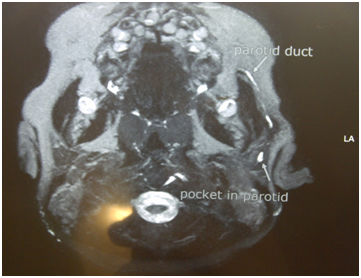

Figure 3 MRI showing the left parotid duct with a collection in the parotid gland.

MRI is also another mode of imaging which can be used to reduce exposure to radiation. MRI enables to visualise larger stones, map the ductal anatomy and to assess the gland. Stones appear as low signal regions (on all sequences) outlined by high signal saliva on T2 weighted images.8 MRI is able to distinguish acute from chronic obstruction as well as glands with incomplete obstruction due to superior tissue discrimination.11 Sialo‒MRI is a diagnostic, non‒invasive, method recently introduced, with promising results, in the evaluation of salivary gland disease.12